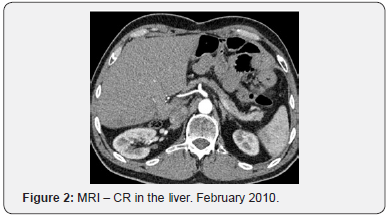

For seven years, from September 2007 till September 2014 she undertook maintenance therapy with bevacizumab (7,5mg/ kg) every three weeks with the cancer disease in remission (Figure 2). The follow up was performed by CT of the neck, thorax and abdomen every 6 months.